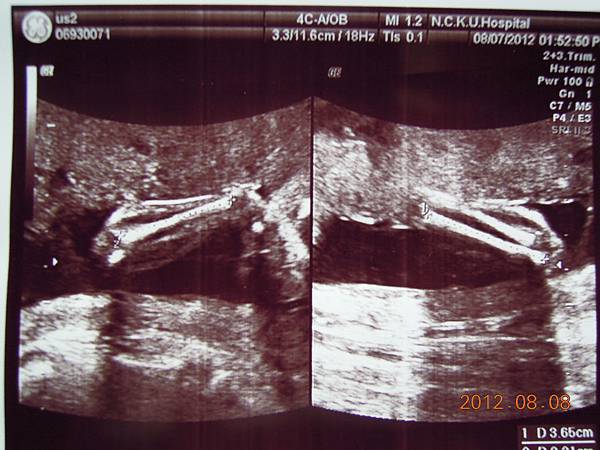

女醫師看起來超熟練,一邊照還會邊跟我解釋,這是逼逼的大腿,小腿,心臟,腎臟.....等等器官,一邊跟我媽聊天,說他生幾個....

除了比較明顯的骨頭可以看的出來,其實我們看不太懂,但是他精熟的技術很快把每個部位的大小都量測出來,我躺在床上看著上頭的螢幕,慢慢欣賞他的每張超音波照片~~

大約檢查了有四五十分鐘,也數了他的手指腳趾,看起來是沒異狀,就叫我等下把報告拿過去門診給游醫師看,還給我ㄧ堆照片,就是下面那些~~

接下來就是他的一堆檢查照片啦~~